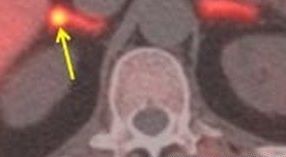

Суть метода заключается в накоплении радиоактивного индикатора только в аденоме Конна и нигде больше.

Радиоактивный индикатор представляет собой радиоактивное соединение, который является безопасным для организма пациента и способным четко отображаться на экране монитора. Специальный радиоактивный индикатор, называемый 11C-metomidate, ученые описывают как "мощный ингибитор стероидогенных ферментов надпочечников ".

Для исследования были набраны 39 пациентов с первичным гиперальдостеронизмом и 5 с нефункционирующих аденомой (часто называемой "случайно выявленной"). Исследователи обнаружили, что с помощью ПЭТ-КТ были точно диагностированы виды аденом у 76% участников и пришли к выводу, что ПЭТ-КТ является чувствительным и специфичным неинвазивным альтернативным методом в диагностике первичного гиперальдостеронизма.